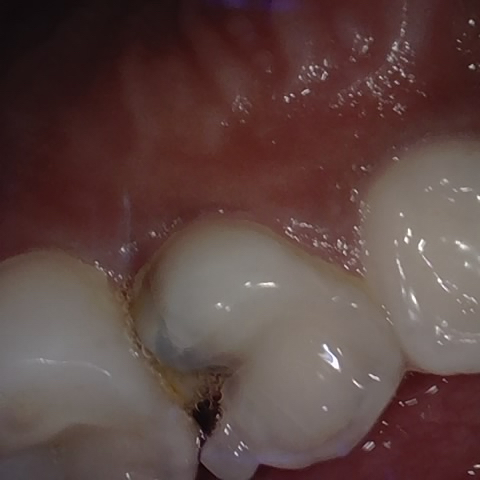

Annotated as "Good"